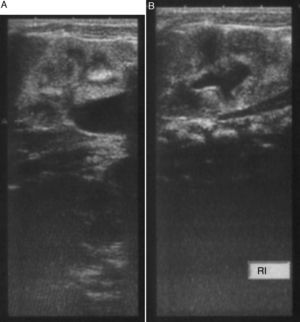

En el ecocardiograma se demostró comunicación interauricular (ostium secundum), conducto arterioso persistente e hipertensión pulmonar. La radiografía simple de abdomen evidenció una imagen radioopaca que ocupaba el mesogastrio y rechazaba las asas intestinales (fig. 2). Se sospechó una megavejiga, sin descartarse obstrucción de los uréteres y la uretra, por lo cual se practicó ecografía renal. En esta se informó ureterohidronefrosis con hidronefrosis izquierda de grado II y derecha de grado III, y aumento difuso de la ecogenicidad renal bilateral, posiblemente por insuficiencia renal crónica (fig. 3); además, se evidenció imagen de masa que ocupaba el mesogastrio y el hipogastrio, de aspecto quístico con partículas en su interior y con aparente comunicación con la vejiga. Se consideró que podía corresponder a un quiste del uraco, por lo que se sugirió practicar una cistouretrografíamiccional.

En el ultrasonido neonatal se demuestra una masa quística en la línea media, con ecos internos por el material mucoide y los detritos celulares5; se puede extender hacia el introito, y acompañarse de edema labial y membrana interlabial en los genitales1. Además, se puede observar hidronefrosis o hidrouréter y otras anomalías renales asociadas8.